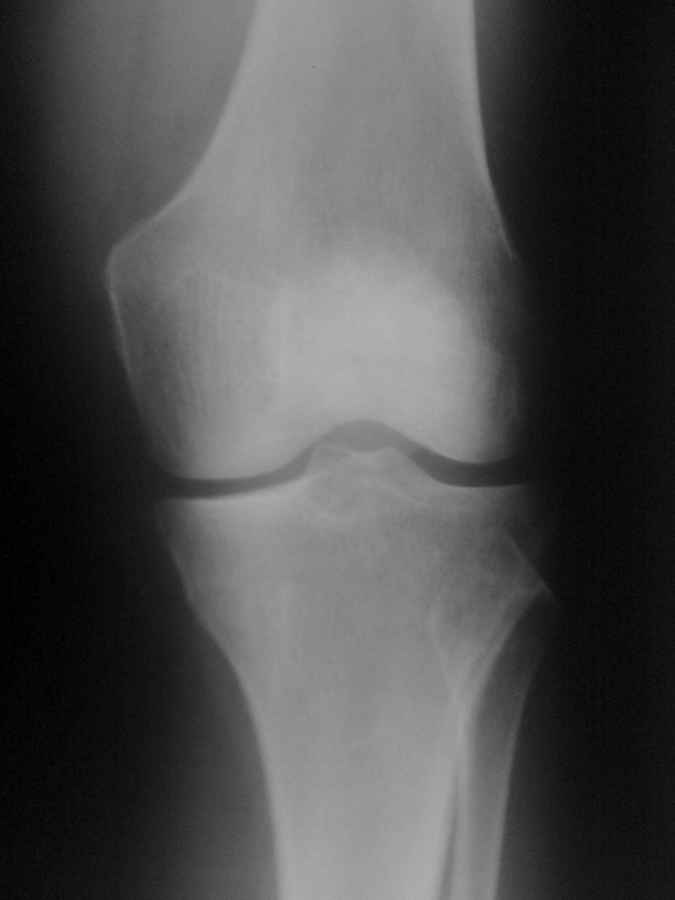

Уважаемые коллеги! 2 месяца назад прооперировал женщину 56 лет (отягощенный анамнез-врач рентгенолог)-артроскопия левого коленного сустава,

субтотальная резекция медиального мениска, тунелизация внутреннего мыщелка бедренной кости (болезнь Кенига). В конце операции в полость сустава введено 10 мл искосила. Послеоперационный период без осложнений. Через 7 дней полный объем движений в коленном суставе с купированием болевого синдрома. Вышла на работу с рекомендациями по ограничение нагрузки.

На контрольных осмотрах через 2 недели 1 месяц, 1,5 месяца без жалоб и объективных осложнений - выпота в суставе нет, отека нет и т.д. Пациентка довольна выполненной операцией. Через 2 месяца после операции на фоне "полного здоровья" утром резкие боли в области внутреннего мыщелка бедренной кости. На осмотре - выпота в суставе нет, движения в полном объеме, умеренно болезненно разгибание, локальная болезненность в одной точке в проекции внутреннего мыщелка бедренной кости - буквально от прикосновения кричит, участок парестезии, гиперемии нет, температурной реакции нет, в анализах - возрастная норма. УЗДГ вен без патологии. МРТ поясничного отдела позвоночника (по направлению невролога - грыжи L5-S1), на ЭНМГ - проводимость в полном объеме, не нарушена.